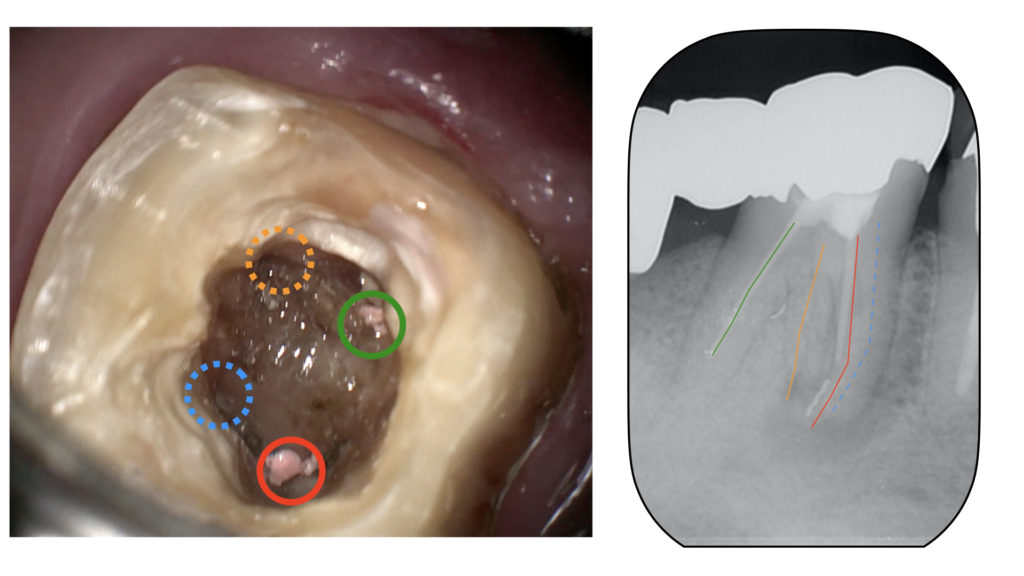

右下が腫れたということで来院されました。 他院で治療していたのですが、根の中にファイルといって治療の道具が折れて残ってしまっており(破折ファイル) 紹介で当院に来て頂きました。 右下のレントゲン写真です。一番奥(画面上左)の歯は骨が根の先まで溶けており、残すこ … 続きを読む マイクロスコープを用いた精密根管治療